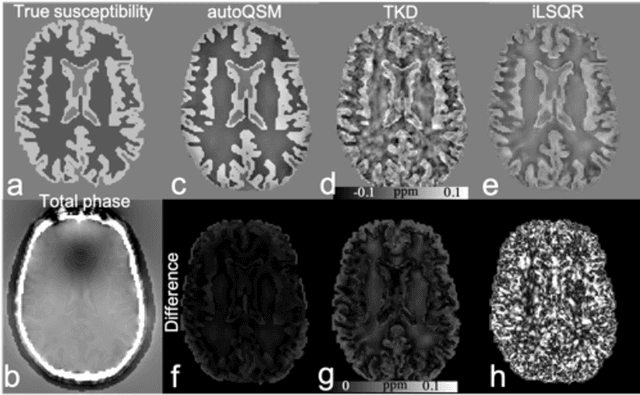

Abstract:Quantitative susceptibility mapping (QSM) estimates the underlying tissue magnetic susceptibility from MRI gradient-echo phase signal and typically requires several processing steps. These steps involve phase unwrapping, brain volume extraction, background phase removal and solving an ill-posed inverse problem. The resulting susceptibility map is known to suffer from inaccuracy near the edges of the brain tissues, in part due to imperfect brain extraction, edge erosion of the brain tissue and the lack of phase measurement outside the brain. This inaccuracy has thus hindered the application of QSM for measuring the susceptibility of tissues near the brain edges, e.g., quantifying cortical layers and generating superficial venography. To address these challenges, we propose a learning-based QSM reconstruction method that directly estimates the magnetic susceptibility from total phase images without the need for brain extraction and background phase removal, referred to as autoQSM. The neural network has a modified U-net structure and is trained using QSM maps computed by a two-step QSM method. 209 healthy subjects with ages ranging from 11 to 82 years were employed for patch-wise network training. The network was validated on data dissimilar to the training data, e.g. in vivo mouse brain data and brains with lesions, which suggests that the network has generalized and learned the underlying mathematical relationship between magnetic field perturbation and magnetic susceptibility. AutoQSM was able to recover magnetic susceptibility of anatomical structures near the edges of the brain including the veins covering the cortical surface, spinal cord and nerve tracts near the mouse brain boundaries. The advantages of high-quality maps, no need for brain volume extraction and high reconstruction speed demonstrate its potential for future applications.